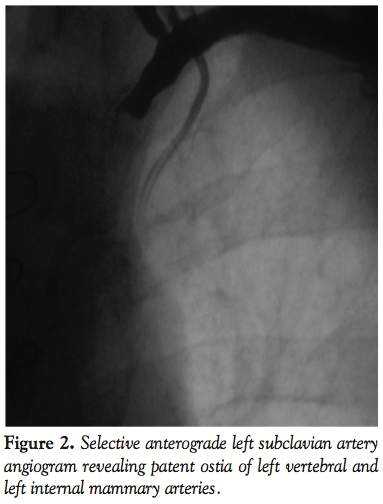

Procedure. The procedure was performed under local anesthesia. A 6 French (Fr) introducer was placed in the right femoral artery and another 6 Fr was placed in the contralateral brachial artery. Left SC artery angiography demonstrated occlusion of the proximal SC artery and flow reversal in the VA and LIMA (Figures 1 and 2). Both carotid arteries were patent, except for 30% plaque in the left internal carotid artery.